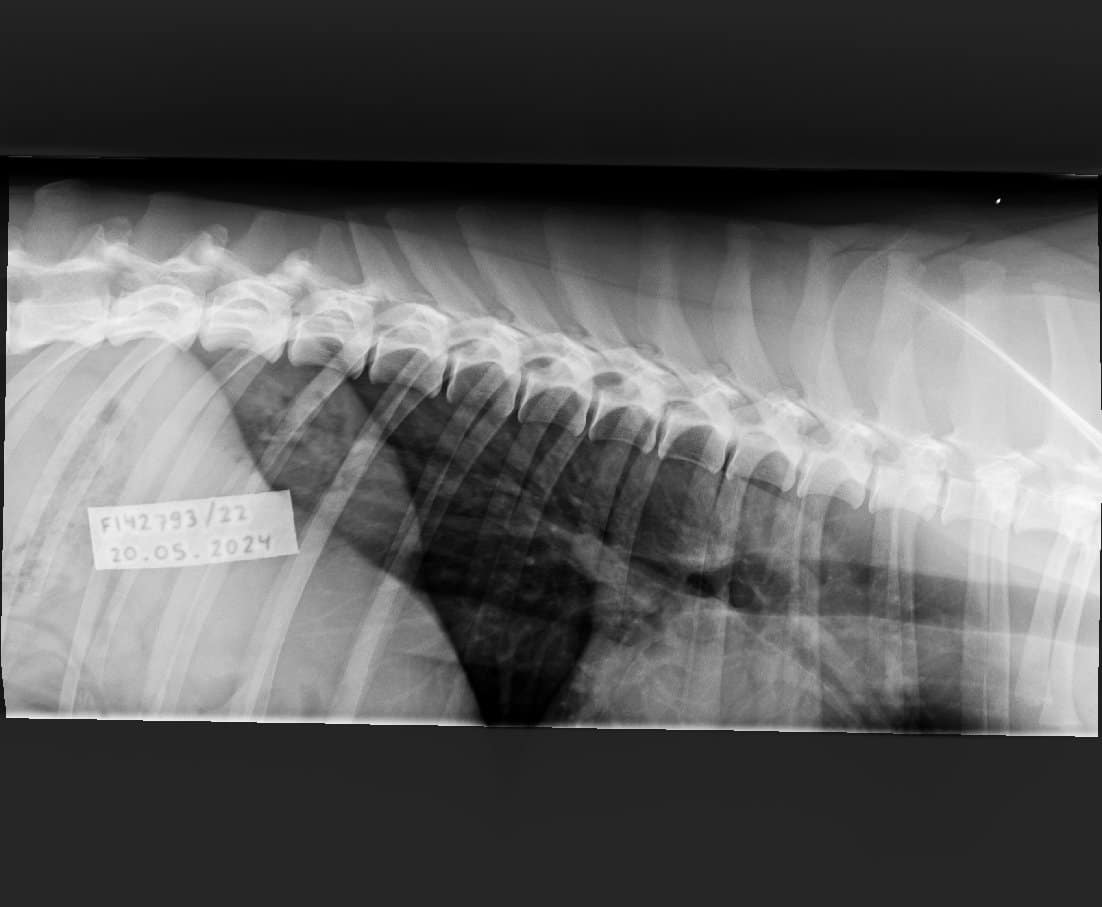

Topin OCD